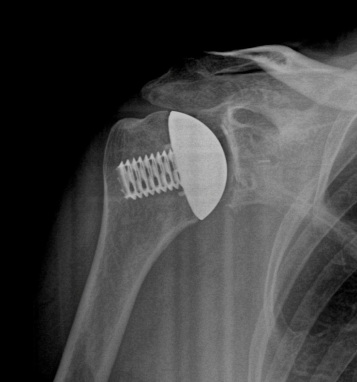

Stemless Total Shoulder Replacement